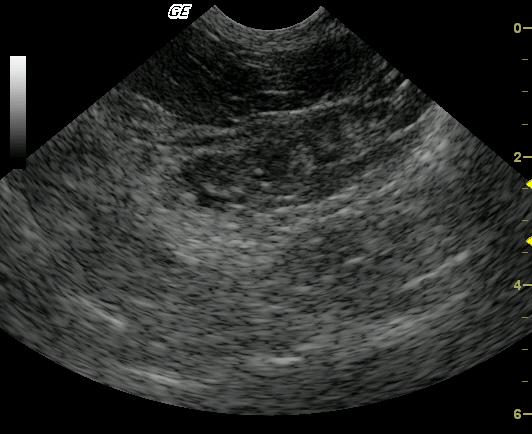

Calculus in left pancreatic duct and pancreatitis in a 13 year old Siamese cat

Due to the pain noted on palpation and pain upon imaging this region, chronic active pancreatitis is likely. Pancreatic duct lithiasis. Minor potential for neoplasia.

A largely hypoechoic mildly heterogenous swollen left pancreatic limb is noted. A calculus is present in the left pancreatic duct.

The patient was focally painful upon imaging the region of the pancreas in which the calculus was noted. The patient improved after 5 days of intravenous fluid therapy with antibiotics and pain management but presented similar manageable signs 6 months post sonogram. Blood parameters returned to normal post therapy. The calculus was never surgically addressed, and the patient remained stable over the next 18 months until he was humanely euthanized due to worsening chronic renal failure.